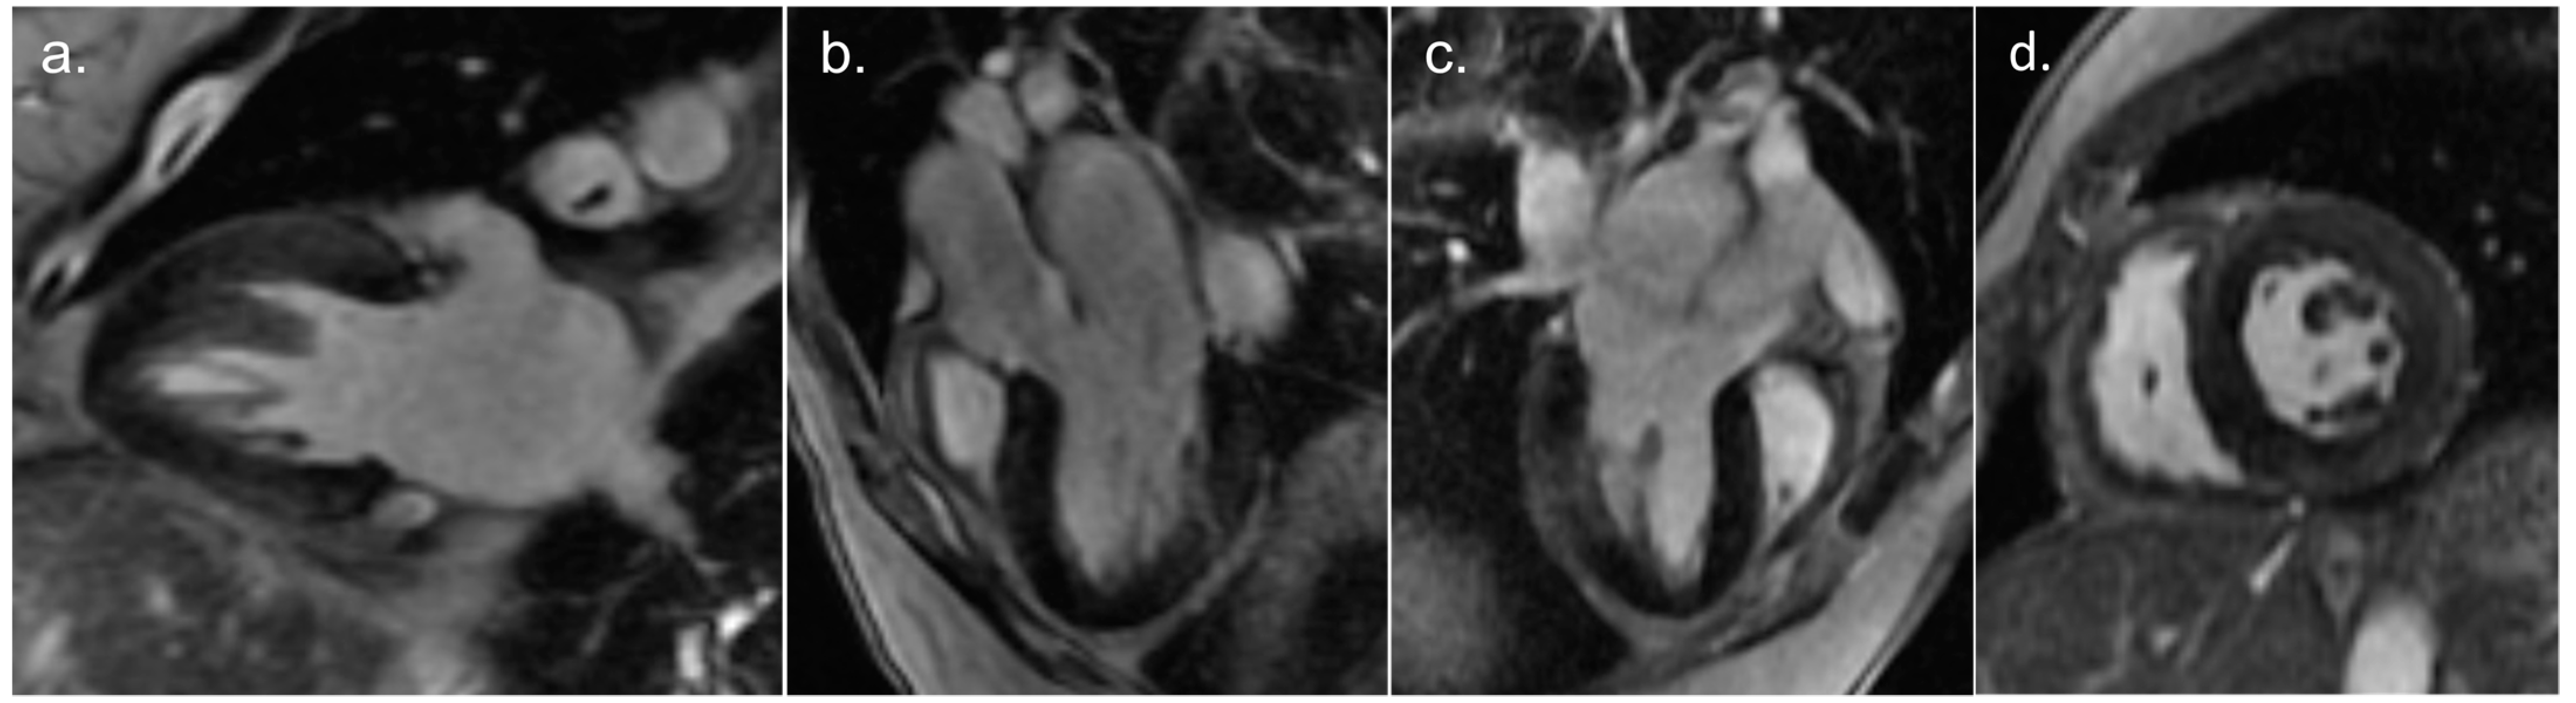

2. Detailed Case Description